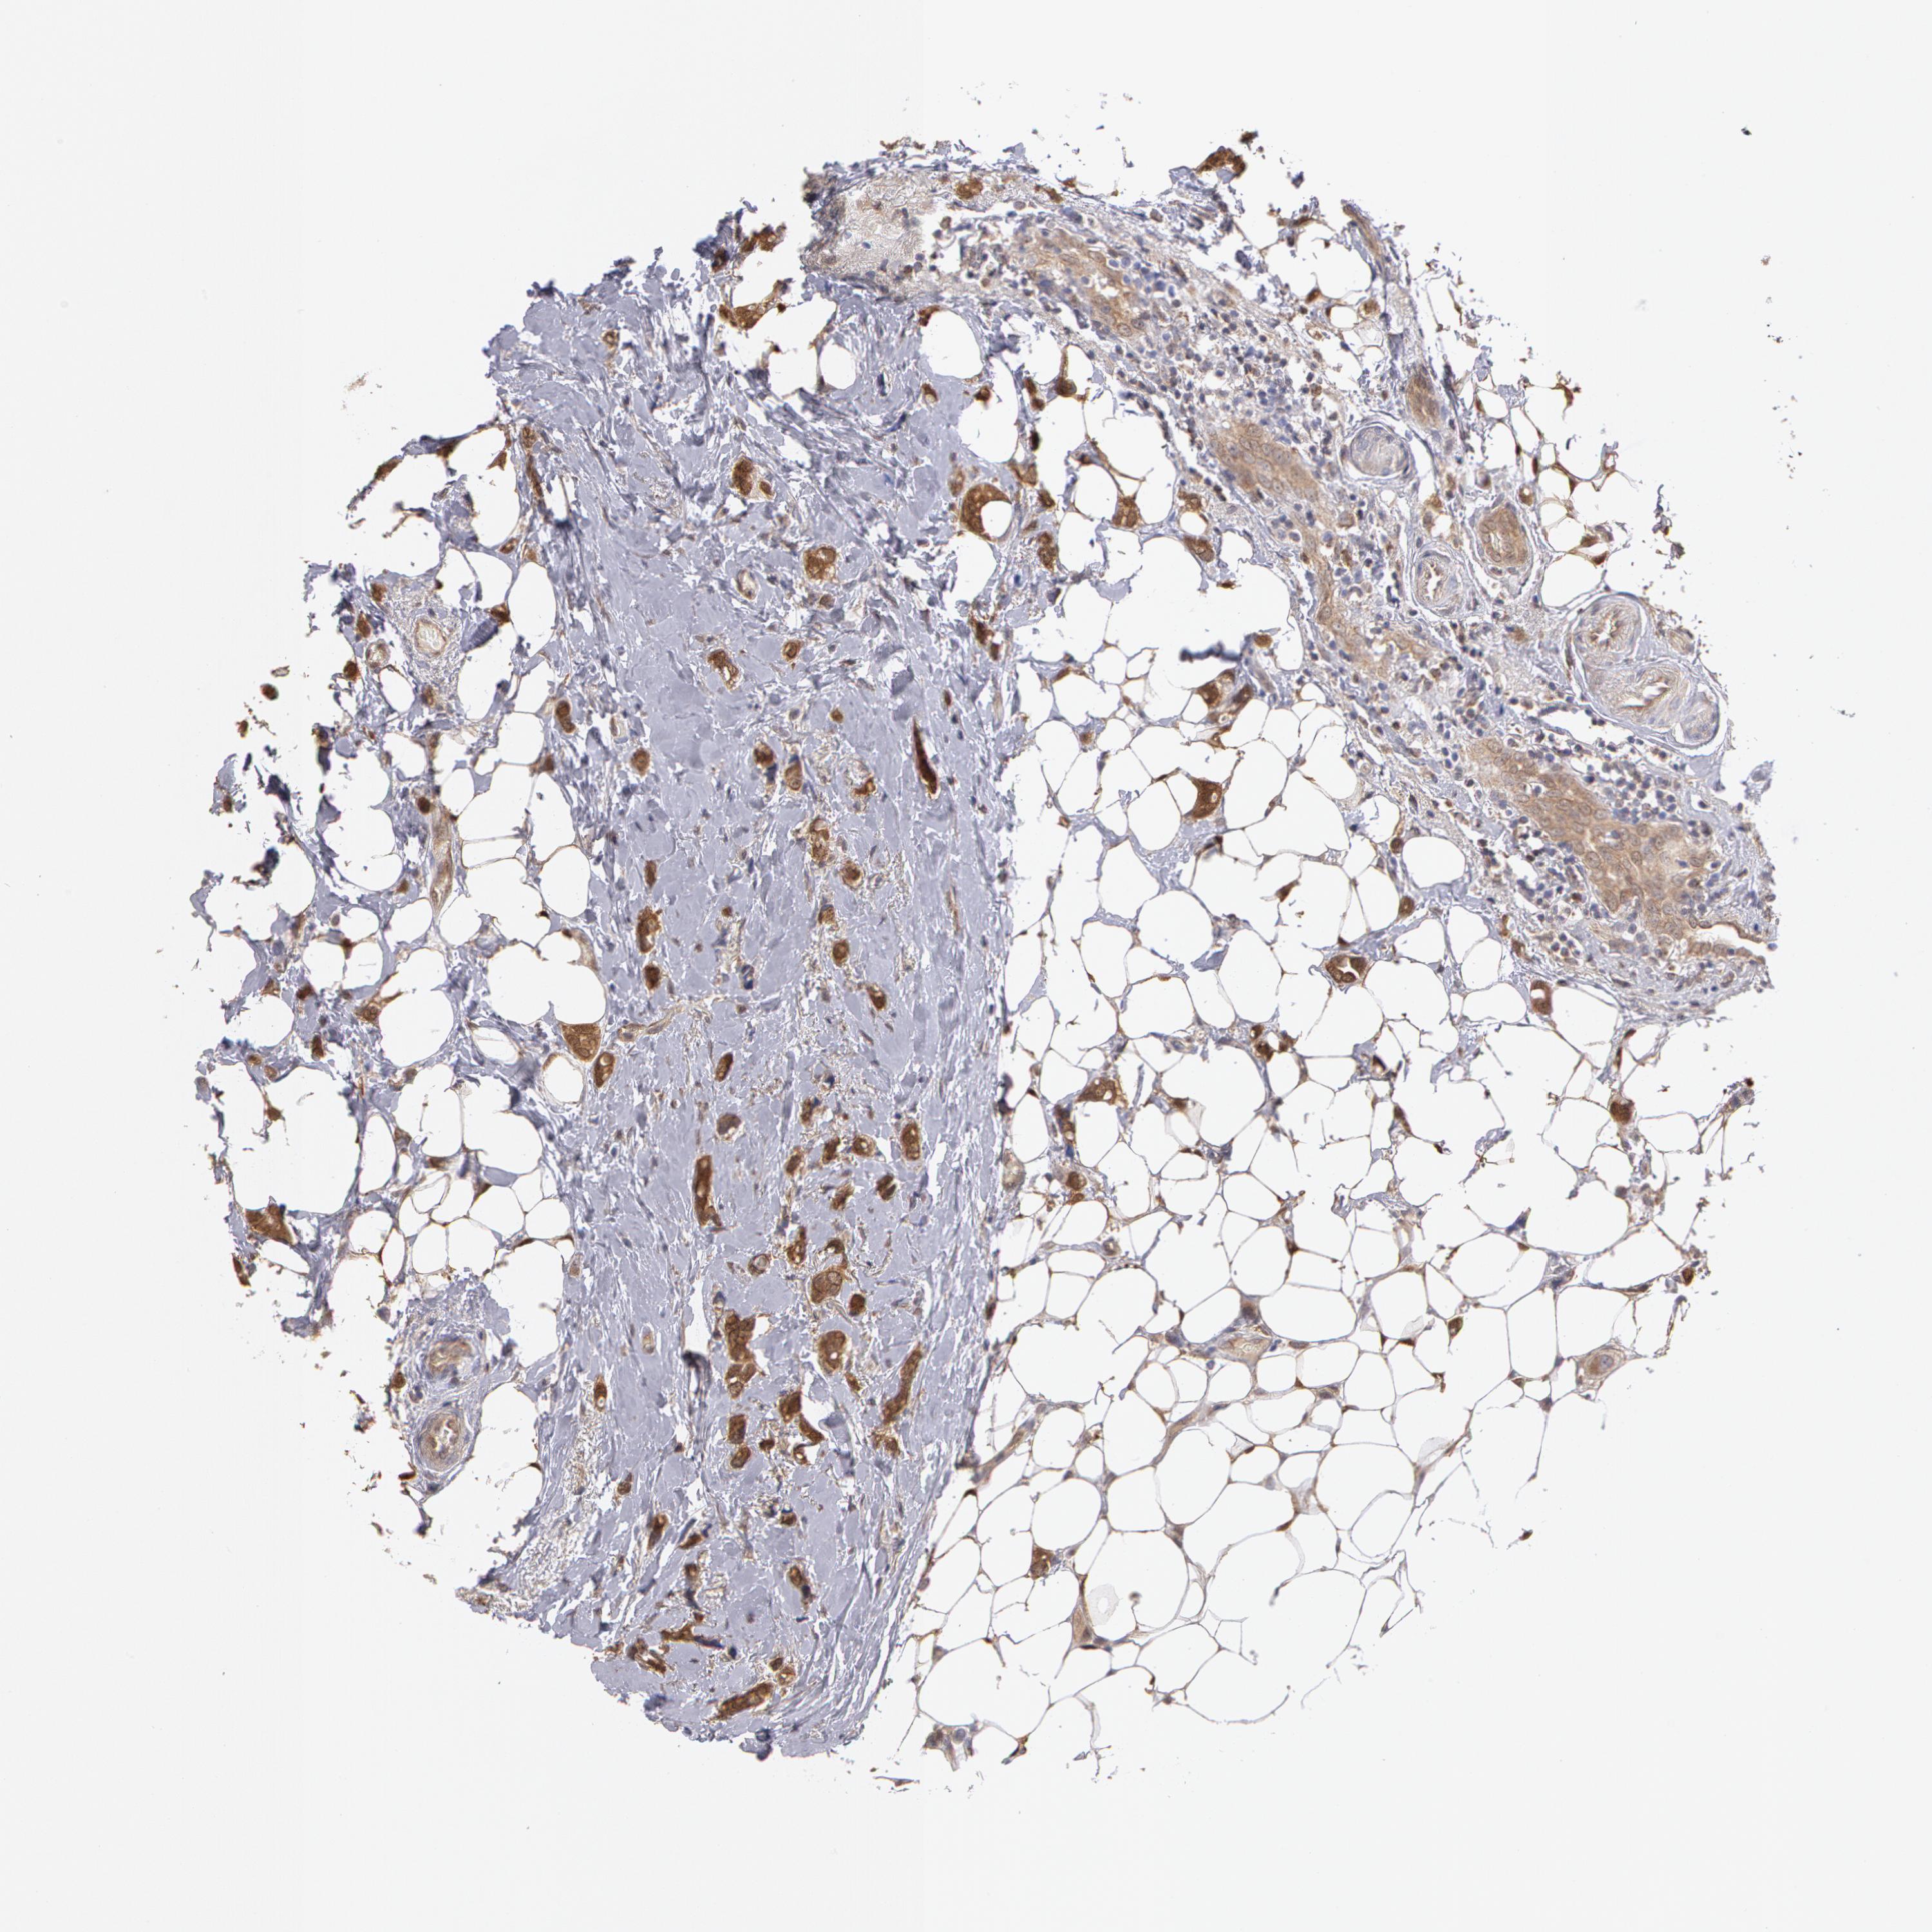

BRCA TCGA BRCA VALIDATION PROTEIN EXPRESSION

ANTIBODIES

AND

VALIDATION